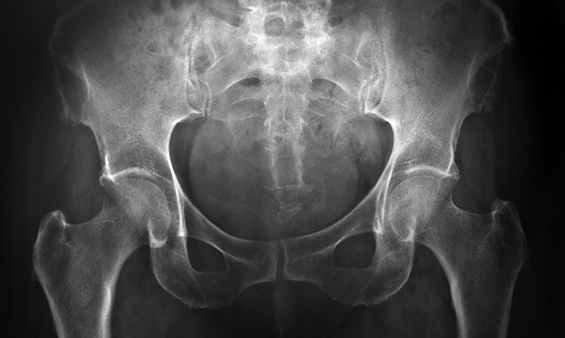

Raio-X Bacia

É um exame de rápida realização e indolor que utiliza raios X para a obtenção de uma imagem radiográfica da bacia.